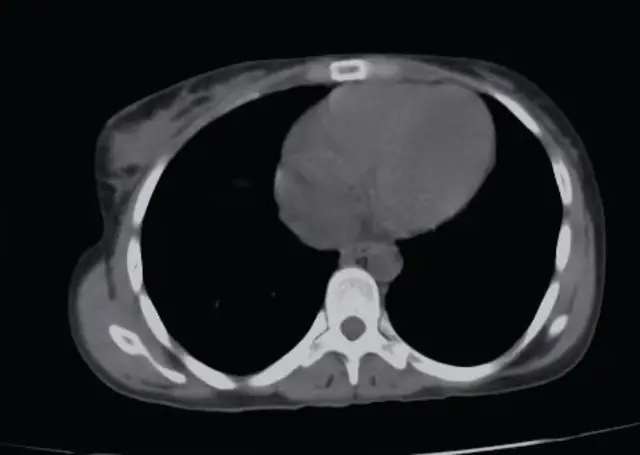

Warbixinta raajada ee soo baxday ayaa ahayd mid aad loola yaabo oo xitaa dhakhaatiirtu ay rumaysan waayeen.

Dr. Sania Zahra, oo samaysay raajada, ayaa u sheegtay Sarvesh in ilmaheeda uu ku jiro beerka. Waxay ahayd xaalad la yaab ku noqotay Sarvesh iyo ninkeeda, Paramveer.

Si loo sii xaqiijiyo warbixintan, waxay tagtay magaalada u dhow ee Meerut, halkaas oo lagu sameeyay raajo kale iyo sidoo kale MRI, laakiin warbixinteedu wali waa sidii hore.

Dr. KK Gupta, oo sameeyay raajada MRI-ga, ayaa BBC-da u sheegay in uusan waligii arag kiis noocaan oo kale ah muddo 20 sano ah.

Sida laga soo xigtay Dr. Gupta, "Waxaa jiray uurjiif 12-toddobaad ah oo ku yaal dhinaca midig ee beerka haweeneyda, kaas oo garaaca wadnaha si cad loo arki karo, xaaladdan waxaa loo yaqaan 'enterohepatic ectopic pregnancy, taas oo ah mid aad u dhif ah. Xaaladdan oo kale, haweenku aad ayay u dhiig baxaan xilliga caadada waxayna u tixgeliyaan inay tahay dhiigga caadada ee caadiga ah, xaaladahan oo kale waxay qaadataa waqti in la ogaado uurka.